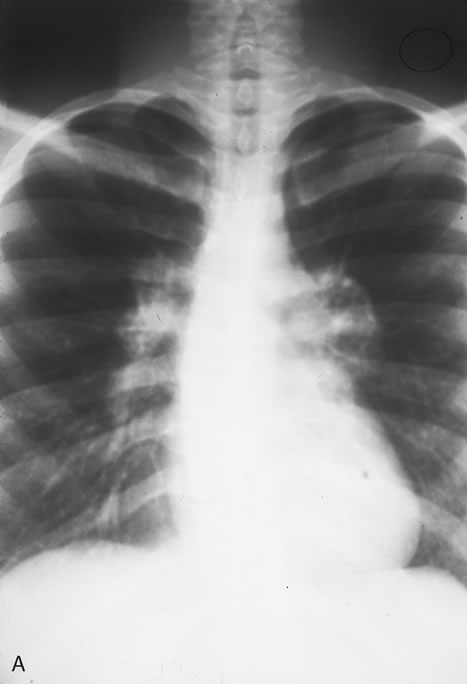

HIV infection results in depletion of T4 cells, which are central to various forms of immune responsiveness. Risk of developing AIDS is inversely related to the absolute T4 cell count. Antigen-responsive T cells become selectively depleted or functionally impaired early in the course of AIDS. There is diminished helper function for B-cell responses, depressed cytotoxic and natural killer cell responsiveness, decreased blast transformation, and decreased lymphokine production. Infected patients' B-lymphocytes spontaneously produce immunoglobulin, resulting in hypergammaglobulinemia, but are unable to produce specific antibody in response to new infections. Anergy is common. HIV also infects other cells that express the CD4 antigen, such as monocytes and macrophages, but is not cytopathic in these cells. HIV has been identified in brain capillary endothelium, oligodendrocytes, astrocytes, lymph node dendritic cells, Langerhans' cells, intestinal mucosa, myocardium, tears, corneal epithelium, aqueous, vitreous, and retina. Clinical manifestations of HIV are protean. Seropositive persons may be asymptomatic. Various acute HIV infection syndromes have been described. An acute mononucleosis-like syndrome, with fever, malaise, rash, lymphadenopathy, pharyngitis, myalgias, and arthralgias, has been noted after recent HIV exposure. Acute neurologic manifestations resembling aseptic meningitis, encephalitis, or focal lesions may be seen.25 AIDS-related complex is a somewhat ambiguous term encompassing features such as chronic fever, night sweats, weight loss, fatigue, generalized lymphadenopathy, chronic diarrhea, and laboratory abnormalities. AIDS-related complex implies an intermediate stage in the spectrum of HIV disease. CDC-defined indicator diseases include HIV encephalopathy, HIV wasting syndrome, CMV disease not involving liver, spleen or lymph nodes (26), progressive multifocal leukoencephalopathy, recurrent Salmonella septicemia, multiple or recurrent serious bacterial infections in children, extrapulmonary myobacterial infection, disseminated histoplasmosis, disseminated coccidioidomycosis, chronic isosporiasis, lymphoid interstitial pneumonia or pulmonary lymphoid hyperplasia in children, primary brain lymphoma, and various non-T–cell non-Hodgkin's lymphomas. Less specifically associated with HIV infection are manifestations of papillomavirus, molluscum contagiosum, VZV, Epstein-Barr virus, hepatitis B virus, chlamydia, gonorrhea, syphilis, campylobacter, pityrosporum, trichophyton, aspergillus, acanthamoeba, entamoeba, giardia, strongyloides, basal cell carcinoma, squamous cell carcinoma, idiopathic thrombocytopenic purpura, cerebrovascular infarction, and intracranial hemorrhage.27–30 Pneumocystis carinii pneumonia once was the most common presentation of AIDS. It is typically of insidious onset, with features including dry cough, dyspnea, and a diffuse bilateral interstitial infiltrate evident on a chest roentgenogram. Typical multifocal fundus lesions have been described. They are yellow-white and have a characteristic pattern on fluorescein angiography (Fig. 10A, 10B, and 10C). Diagnosis is made by demonstrating the protozoon via sputum induction, bronchioalveolar lavage, and transbronchial or open-lung biopsies. Treatment modalities include trimethoprim-sulfamethoxazole (TMP-SMX).31 Kaposi's sarcoma is much more frequent in male homosexuals and bisexuals than in other patients with AIDS. Cutaneous lesions are usually red or violaceous, palpable, and nonblanching papules, nodules, or plaques, often appearing on the hard palate, nose, eyelid, and conjunctiva (Fig. 11). Visceral and lymph node involvement is common and often clinically silent. Biopsy specimens show proliferation of small, incompletely formed blood vessels lined by unusually large endothelial type cells, with extravasated red blood cells and infiltrates of spindle-shaped cells. Chemotherapy with etoposide, Vinca alkaloids, or interferon-α may be indicated in advanced cases.28